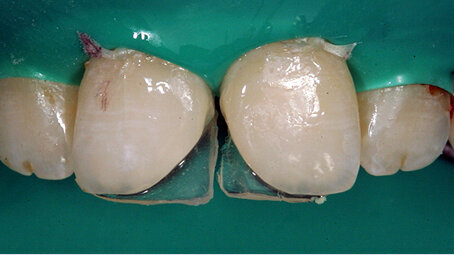

Dvě kazuistiky přímé kompozitní dostavby frontálních zubů s pomocí kompozitního materiálu Charisma Topaz (Heraeus Kulzer). Zkrácená verze – celý článek naleznete na www.stomateam.cz, nebo v časopise StomaTeam 5/2016 (pozn. red.).

Frontální výplně jsou velice individuálním typem ošetření, při němž terapeutické možnosti závisí především na velikosti defektu a estetických požadavcích pacienta. Přestože nepřímé keramické náhrady jsou vysoce kvalitním univerzálním „kouzelným“ výstupem, který umožňuje vložit estetické a funkční problémy do rukou zubního technika, vyžadují obvykle výrazně masivnější základní konstrukci než přímé kompozitní výplně a jsou také výrazně dražší. Kromě aspektu nákladů však přímé výplně skórují i z hlediska přístupu „jedné návštěvy“, tj. že pacient nepotřebuje žádnou provizorní náhradu a může jednoduše odejít domů s definitivní výplní. V zásadě totéž je možné se systémem Cerec, ale požadavky na zbytkovou hmotu zubu a náklady zde zůstávají.

Takto velké rekonstrukce funkce frontálních zubů hovoří samy za sebe díky metaanalýze zveřejněné na toto téma, které se podařilo prokázat míru průměrné roční ztráty kompozitních výplní mezi 0 až 4,1 %. Protože hlavním důvodem selhání větších výplní kavit IV. třídy bylo jejich odlomení, je prokázán význam volby stálejších kompozitních materiálů, které mají vysokou pevnost v lomu.